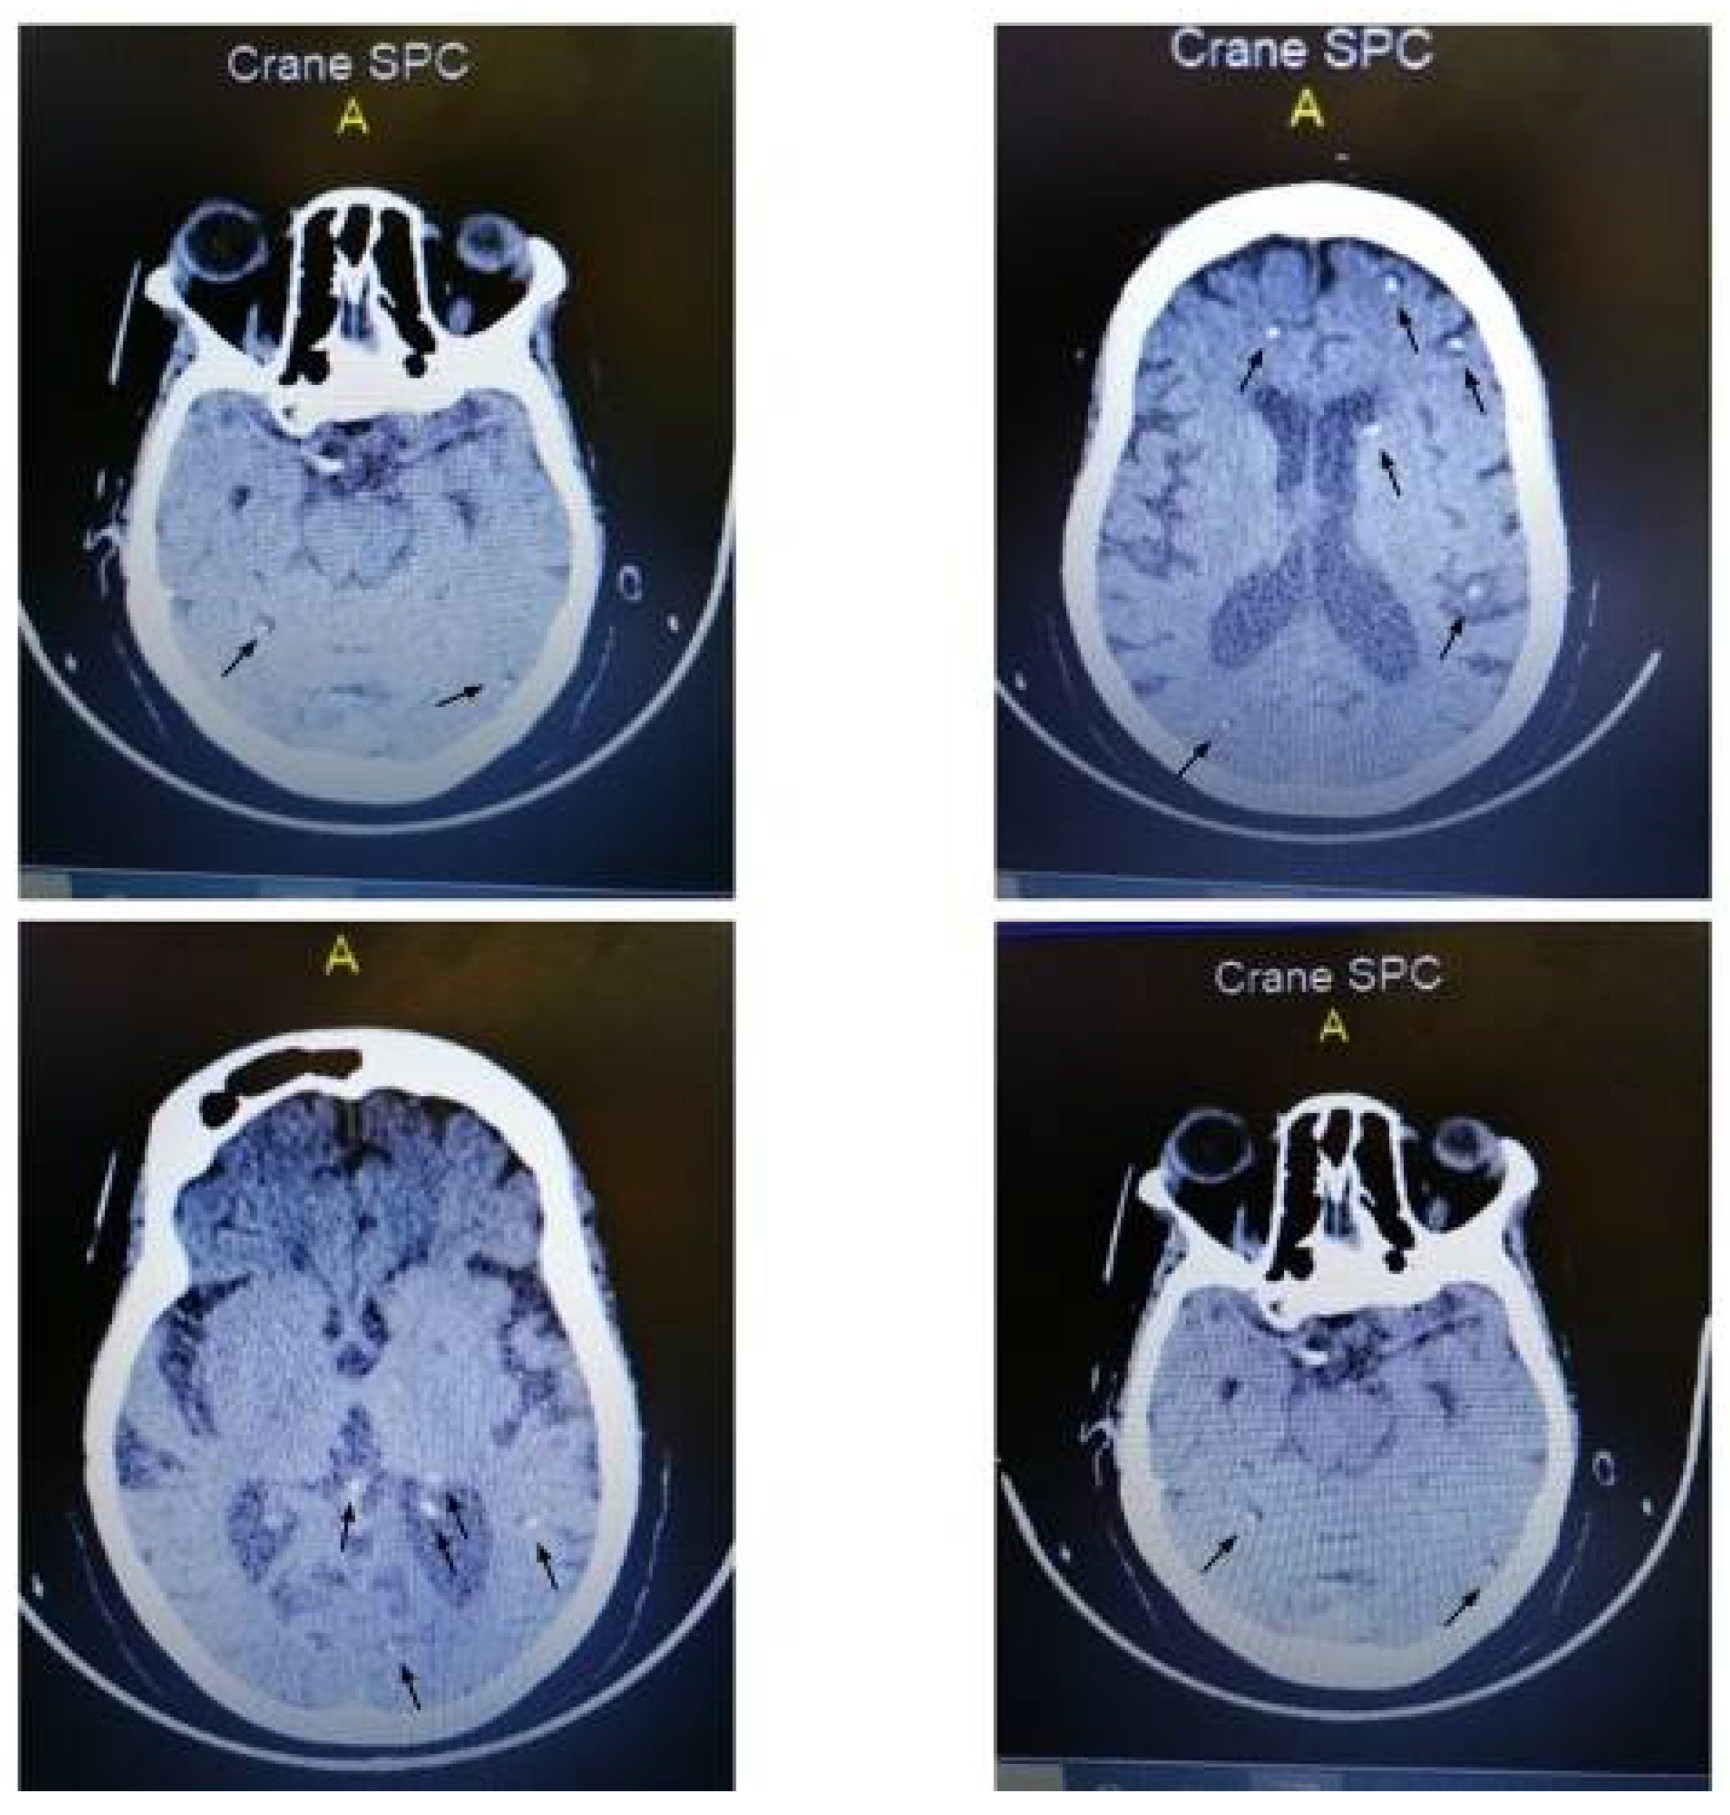

2. Case Presentation